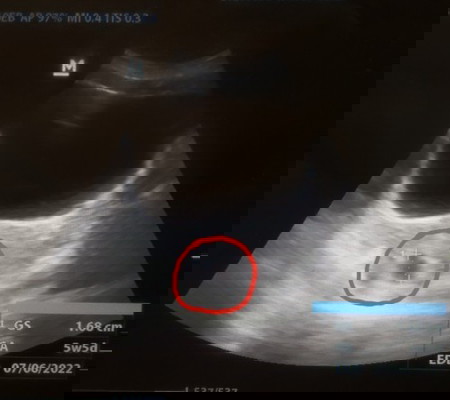

Usia kehamilan dari hasil USG berbeda dengan perhitungan HPHT

Ini kehamilan pertama saya. Haid saya teratur, siklusnya 30-33 hari. Kalau berdasarkan HPHT, seharusnya usia kehamilan sudah 8w6d. Tapi saat USG ternyata masih 5w5d. Sudah ada kantung kehamilan, tapi janin belum kelihatan. Tapi bidannya tidak khawatir, katanya memang wajar kalau belum kelihatan di usia kehamilan segini. Saya berpikir positif saja, karena selama ini juga tidak ada keluhan seperti nyeri atau spotting. Saya hanya heran kenapa usia kehamilan dair hasil USG dengan HPHT bisa berbeda sampai 3 minggu ya? Mohon share pengalaman dan wawasannya ya, Bunda. Terima kasih. #firstbaby #pleasehelp #ingintahu